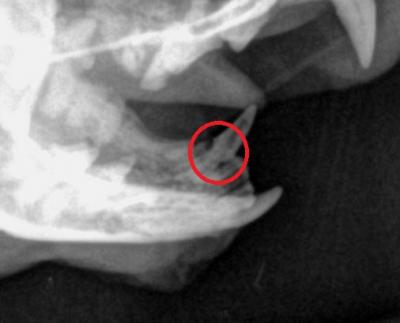

Našim pacientem byla Fanynka, jedenáctiletá kočka, která byla přivedena na kliniku z důvodu hubnutí a progredující inapetence. Dásna nebyla výrazně postižena, avšak patrná byla léze na spodním špičáku. Následný rtg snímek odhalil resorpční lézi.

Resorpční léze jsou charakteristiké mimojiné i lýzou zubního kořene. Na rtg snímku vidíte špičák Fanynky. Vymizení tkáně zubního kořene je zvýrazněno kroužkem. Přesně toto místo je náchylné k odlomení korunky zubu.